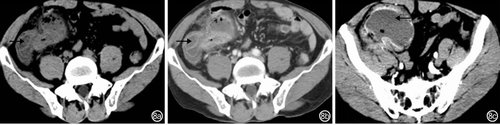

良性间质瘤患者CT检查主要表现为局限性中重度肠壁增厚,肠腔内、肠壁内或浆膜下软组织包块病变肠壁明显不均匀强化,呈现“环靶征”(图2);肠外主要表现为肠套叠、肠梗阻征象:肠管扩张、积液、积气。(点击图片可查看原图)

图2 空肠良性间质瘤(肠道内壁间质瘤继发空肠肠套叠)患者CT检查特征:2a:平扫空肠内壁呈结节状不均匀性增厚(←),密度不均匀;2b:动脉期局部肠壁明显不均匀强化,呈“环靶征”(←);2c:静脉期病变近段肠壁重度增厚(→)

恶性间质瘤患者CT检查表现为局限性或节段性中重度肠壁不均匀性增厚,肠腔内、肠壁内或浆膜下软组织包块、病变中心坏死液化,病变肠壁明显不均匀强化(图3);肠外主要表现为肠系膜和大网膜转移、肝转移。(点击图片可查看原图)

图3 空肠恶性间质瘤患者CT检查特征:肠壁局限性不均匀性增厚,内见坏死液化灶(→),腹腔积液(↓)和肠系膜增厚(↑) 3a:平扫肠壁局限性不均匀性增厚、边界不清(←);3b:动脉期局部肠壁明显不均匀强化;3c:静脉期肠壁强化程度减弱